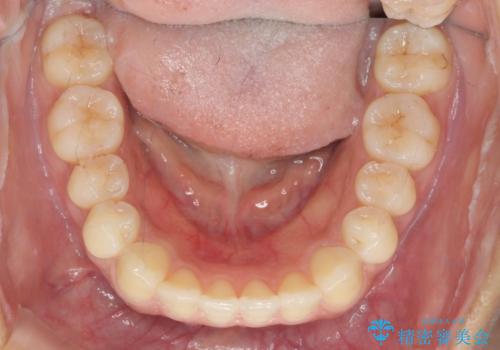

- 上下前歯のすれ違い、ねじれのある歯並びの矯正治療を求めて来院されました。

上顎前歯のみの部分ワイヤー治療を約6ヶ月行い、ねじれの問題を解決したのち、マウスピース矯正で細かな歯列を整えていきます。